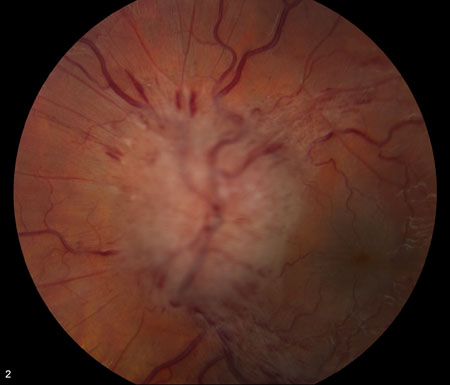

Idiopathic intracranial hypertension

Frisén stage 4

From the personal collection of Dr M. Wall; used with permission